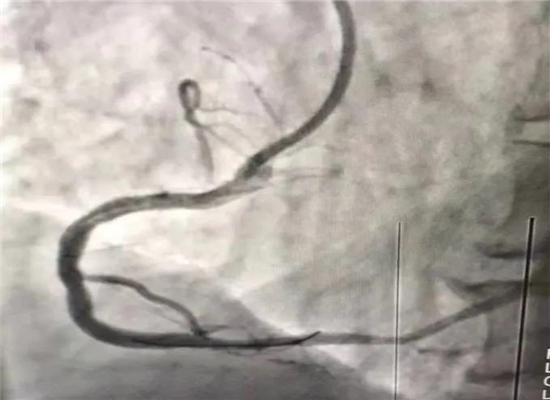

介入手术前

介入手术后